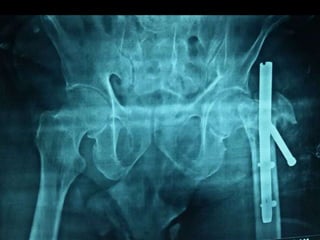

Failed

Subtrochanteric

fracture fixation

with broken DCS

and plate

After 51 days